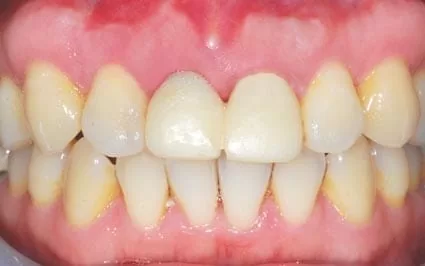

三個月後換上臨時牙套進行牙齦塑型,慢慢將植牙處的牙齦調整到如同原來長出的牙齒般自然。

最後接上植牙柱心,製作全瓷冠,瞧! 完全看不出來曾經接受植牙吧。